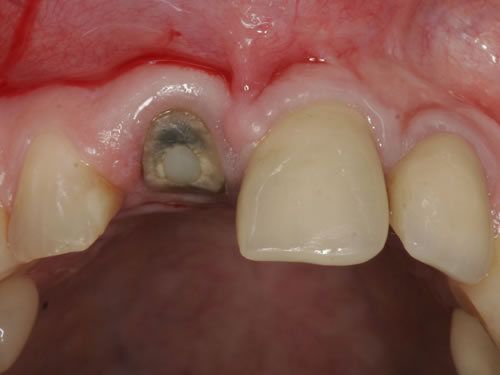

7.4. Weichgewebsersatz

Häufig führt ein Zahnverlust zu einem Verlust von Knochen (Hartgewebe) und der bedeckenden Schleimhaut (Weichgewebe). Besonders im sichtbaren ästhetisch sensiblen Bereich ist es aber notwendig, dass sowohl Hart- als auch Weichgewebe so wiederhergestellt wird, dass im Idealfall das Zahnimplantat mit seiner Krone dem Aussehen des ehemaligen gesunden Zahn entspricht. Als Erfolgskriterien werden aus zahntechnischer Sicht die Form, Farbe und Größe der individuellen Krone angesehen. Aus medizinischer Sicht gibt es wichtige Erfolgskriterien, die die Implantatposition, die Implantatlänge, den Implantatdurchmesser, den Zahnfleischrand im Vergleich zum Nachbarzahn und die Zahnfleischpapillen zwischen den Zähnen beinhalten. Zusätzlich braucht man ein zahntechnisches Labor, das mit der Keramikverarbeitung ein natürliches Aussehen gestalten kann. Nur, wenn alle Parameter perfekt sind, ist das Ergebnis perfekt. Das macht den Einzelzahnersatz im Oberkieferfrontzahngebiet zu einer echten Herausforderung.

Nach der Entfernung von Zähnen kommt es schnell zu Knochenverlust (Resorptionen) und entsprechendem Verlust von Schleimhaut. Die Schleimhaut kann durch bestimmte Operationstechniken wiederhergestellt werden, in dem man freie oder gestielte Bindegewebstransplantate z. B. vom Gaumen entnimmt und das fehlende Material so ersetzt. Das Weichgewebe kann in unterschiedlichen Behandlungsphasen korrigiert werden. In vielen Fällen wird es während der Implantation oder bei der Freilegung verbessert. Manchmal müssen Feinkorrekturen auch nach Eingliederung der fertig gestellten Krone erfolgen, wenn ästhetische Einbußen vorliegen. Häufig hat die Zahnfleischkorrektur auch noch einmal die Änderung der endgültigen Krone zur Folge (Abb. 7.14, 7.15).

Aus der bekannten Tatsache, dass Knochen- und Weichgewebsverlust nach Zahnentfernungen stattfinden und dass der Verlust grösser ist, je länger die Entfernung des Zahnes her ist, wurde die zeitnahe Implantation überlegt. So kann das Hart- und Weichgewebe durch das neue gesetzte Implantat gestützt und muss nicht zu einem späteren Zeitpunkt ersetzt werden. Für eine Sofortimplantation müssen aber wichtige Kriterien erfüllt sein. Hierzu zählen entzündungsfreier Zahnverlust, gute und dicke Zahnfleischform und keine entzündlichen Veränderungen des Zahnhalteapparates. Wenn diese wichtigen Parameter erfüllt sind, dann ist eine Sofortimplantation möglich. Leider sind die Voraussetzungen nur in sehr wenigen Fällen so, da selten gesunde, entzündungsfreie Zähne entfernt werden. In der Bildergalerie wurde ein tief kariöser Zahn ideal entfernt, ein Implantat als Sofortimplantat eingesetzt und mit einer provisorischen Kunststoffkrone versorgt. Nach Abheilung erfolgte die definitive prothetische Versorgung mit einer Vollkeramikkrone (Abb. 7.16, 7.17).

Abb. 7.16: Sofortimplantat eines oberen mittleren Schneidezahnes, mit eingebautem Implantataufbau.

Abb. 7.17: Zementierte definitive Krone nach Einwachsen des Implantates (3 Monate später).